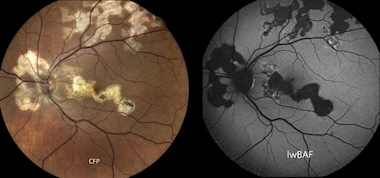

Published in Biomolecules, the review found FAF to be "an underestimated imaging technique" for detecting pathological abnormalities within the retina and the choroid.

FAF can offer a route to studying the disease in all its forms, since it detects autofluorescence not only from the lipofuscin pigment found in the eye's retinal pigment epithelium (RPE) layer, but also other intrinsic fluorophores that may appear as a result of the pathologic processes underway.

The study determined that FAF is a reliable method for detecting atrophy of the RPE layer, which can be more difficult to delineate with other imaging modalities, according to the researchers. And FAF is not only useful for identification of damaged RPE, but also for monitoring of retinal lesions and scars.

The FAF technique can also be versatile, since using different wavelengths of light can reveal different different details of uveitis and the tissues within which it is occurring.

The UKB review compared the autofluorescence produced by different incident wavelengths and found that a combination of wavelengths can yield additional information about the underlying forms of uveitis.

"FAF can aid diagnosing, distinction, and monitoring of different uveitis entities, especially as part of a multimodal imaging approach," concluded the authors. "Applicability of FAF in uveitis is even greater when using a combination of short- and long-wavelength illumination."